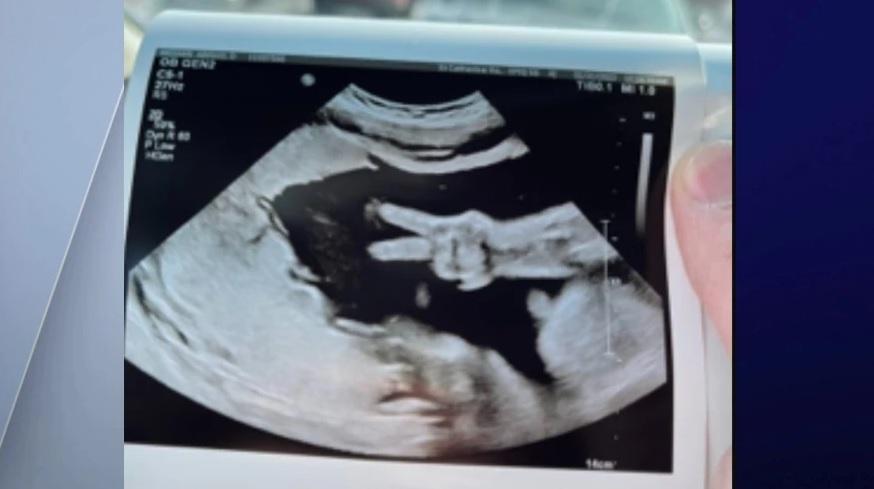

女兒在媽媽的肚裡突然展示V字手勢,給父母驚喜。(互聯網)

凱爾說,醫護幫太太做超聲波檢查時,到不同位置觀察胎兒狀況,突然間兩隻手指就彈起,醫護也大感驚訝,立即轉過頭望向他們夫婦倆,大家都笑作一團。

從超聲波影像可見,胎兒比出V字手勢。凱爾表示,「醫護說他們從未見過這樣的事,這是獨一無二的。」